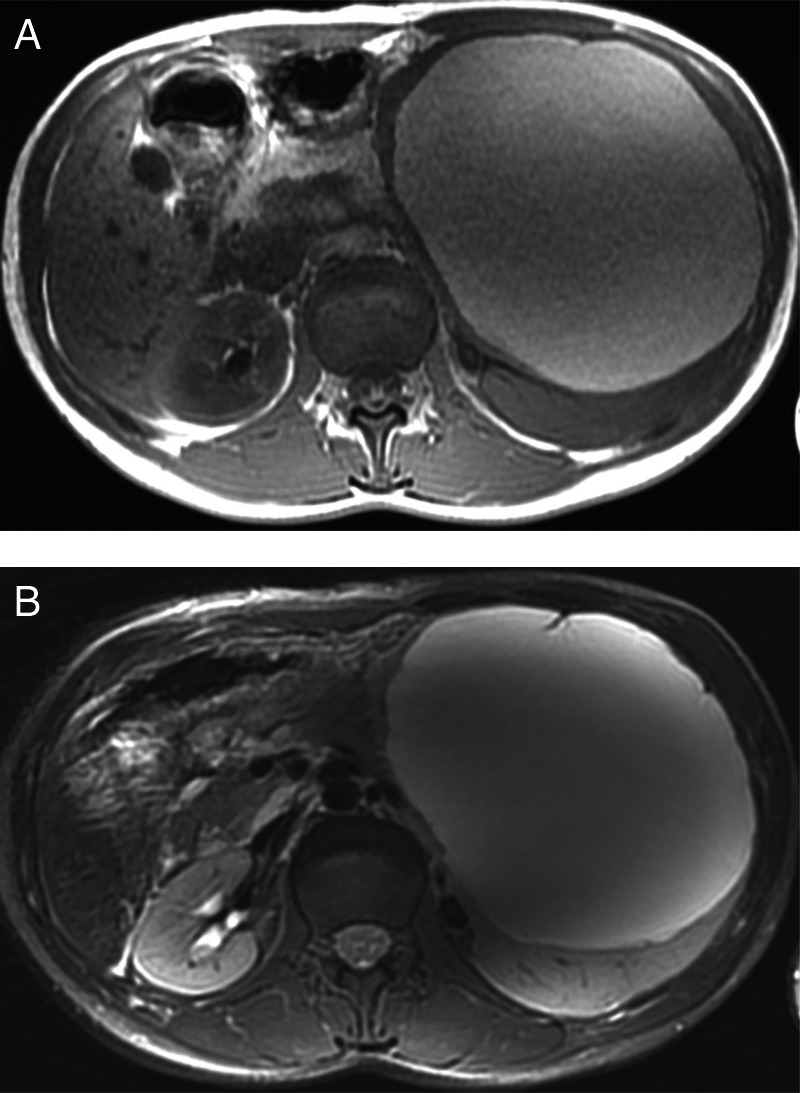

On MRI (figure 2), performed with a GE Discovery MR750 3.0T using LAVA sequences, diffusion, T1-weighted and T2-weighted images, the cystic mass showed high-signal intensity on T1-weighted and T2-weighted images. Within the cyst, thin septations and calcifications were noted. No enhancement in the cyst wall and no signal on diffusion were seen.

Figure 2.

MRI showing the cystic mass with high-signal intensity on T1-weighted (A) and T2-weighted (B) images.